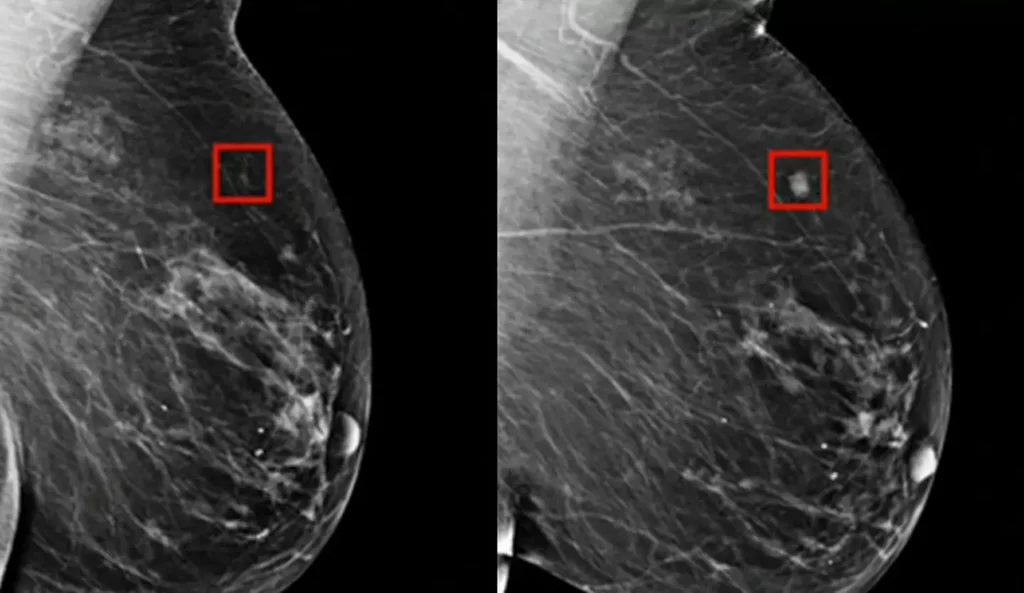

Një program i ‘AI’ zbuloi me sukses kancerin e gjirit tek një grua katër vjet përpara se të zhvillohej. Ndërsa disa përparime të ‘AI’ mund të jenë frikësuese, ato gjithashtu mund të bëjnë një të mirë të konsiderueshme, të tilla si ndihma në diagnostikimin e hershëm të sëmundjeve. ‘AI’ tani po përdoret në shqyrtimin e kancerit për të identifikuar problemet e mundshme shumë kohë përpara se ato të bëhen të dëmshme.

Dr. Larry Norton i Qendrës së Gjirit Lauder shpjegoi për CNN se ‘AI’, e cila ka ekzistuar që nga fundi i viteve 1990, po bëhet më e dobishme në identifikimin e problemeve të mundshme shëndetësore. AI mund të ndihmojë radiologët duke identifikuar zonat në mamografi që kanë nevojë për ekzaminim më të afërt.